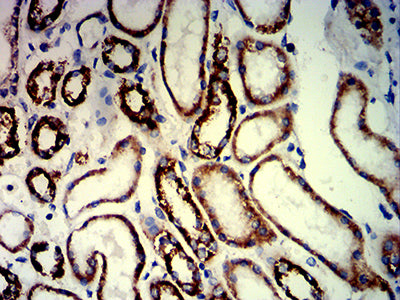

分类: 科研抗体货号: 31988别名: UV20; COFS4; RAD10应用: WB,IHC,FCM反应种属: Human, Mouse